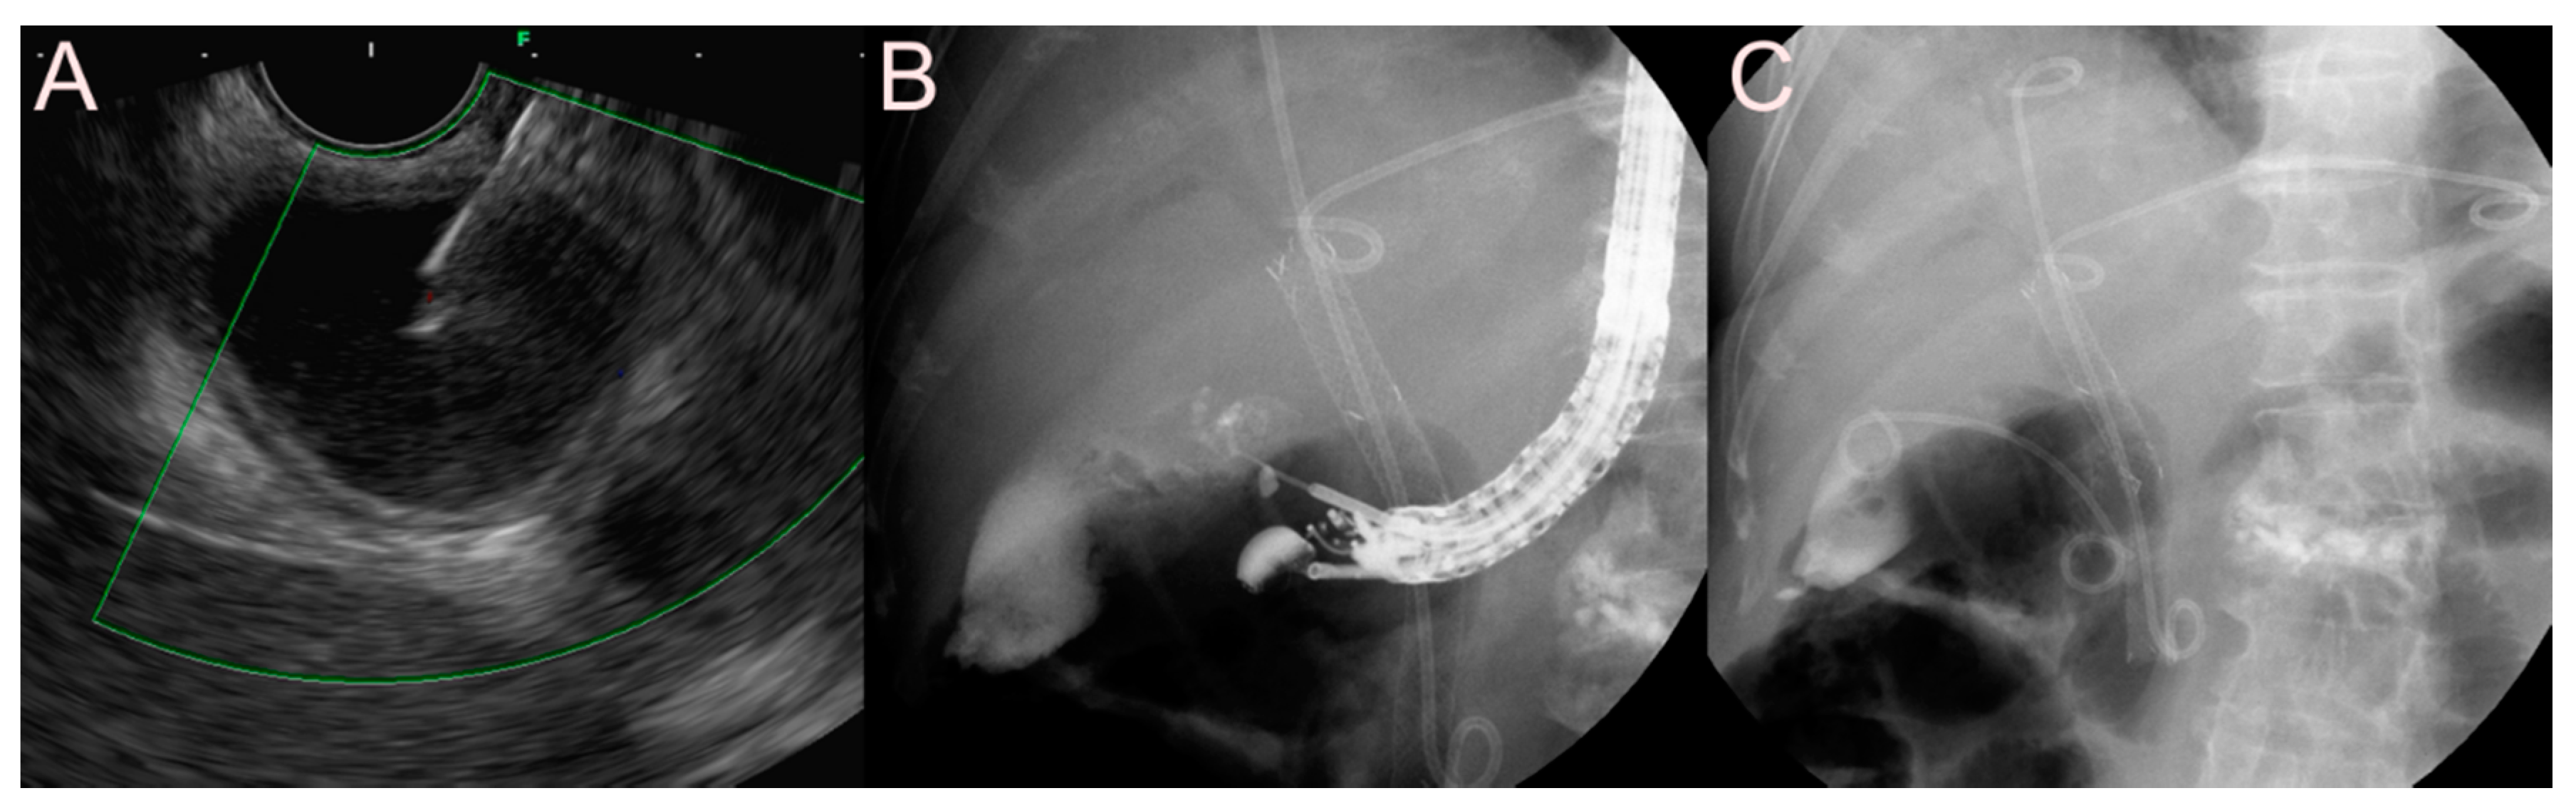

2.3.3. Use of the LAMS